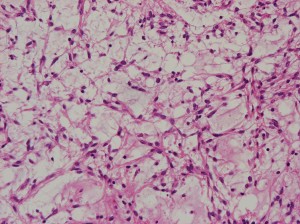

生後6ヶ月の視神経交叉腫瘍です。左では,monomorphous bipolar cellsとmucoid matrixが豊富に見られます。右では細い血管の周囲に腫瘍細胞が集簇するangiocentric patternが特徴的です。粘液性分が多くドロドロした腫瘍です。